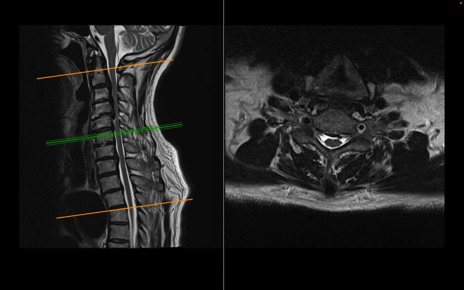

頚椎MRI

T2WI(横断像)

T2WI(矢状断像)